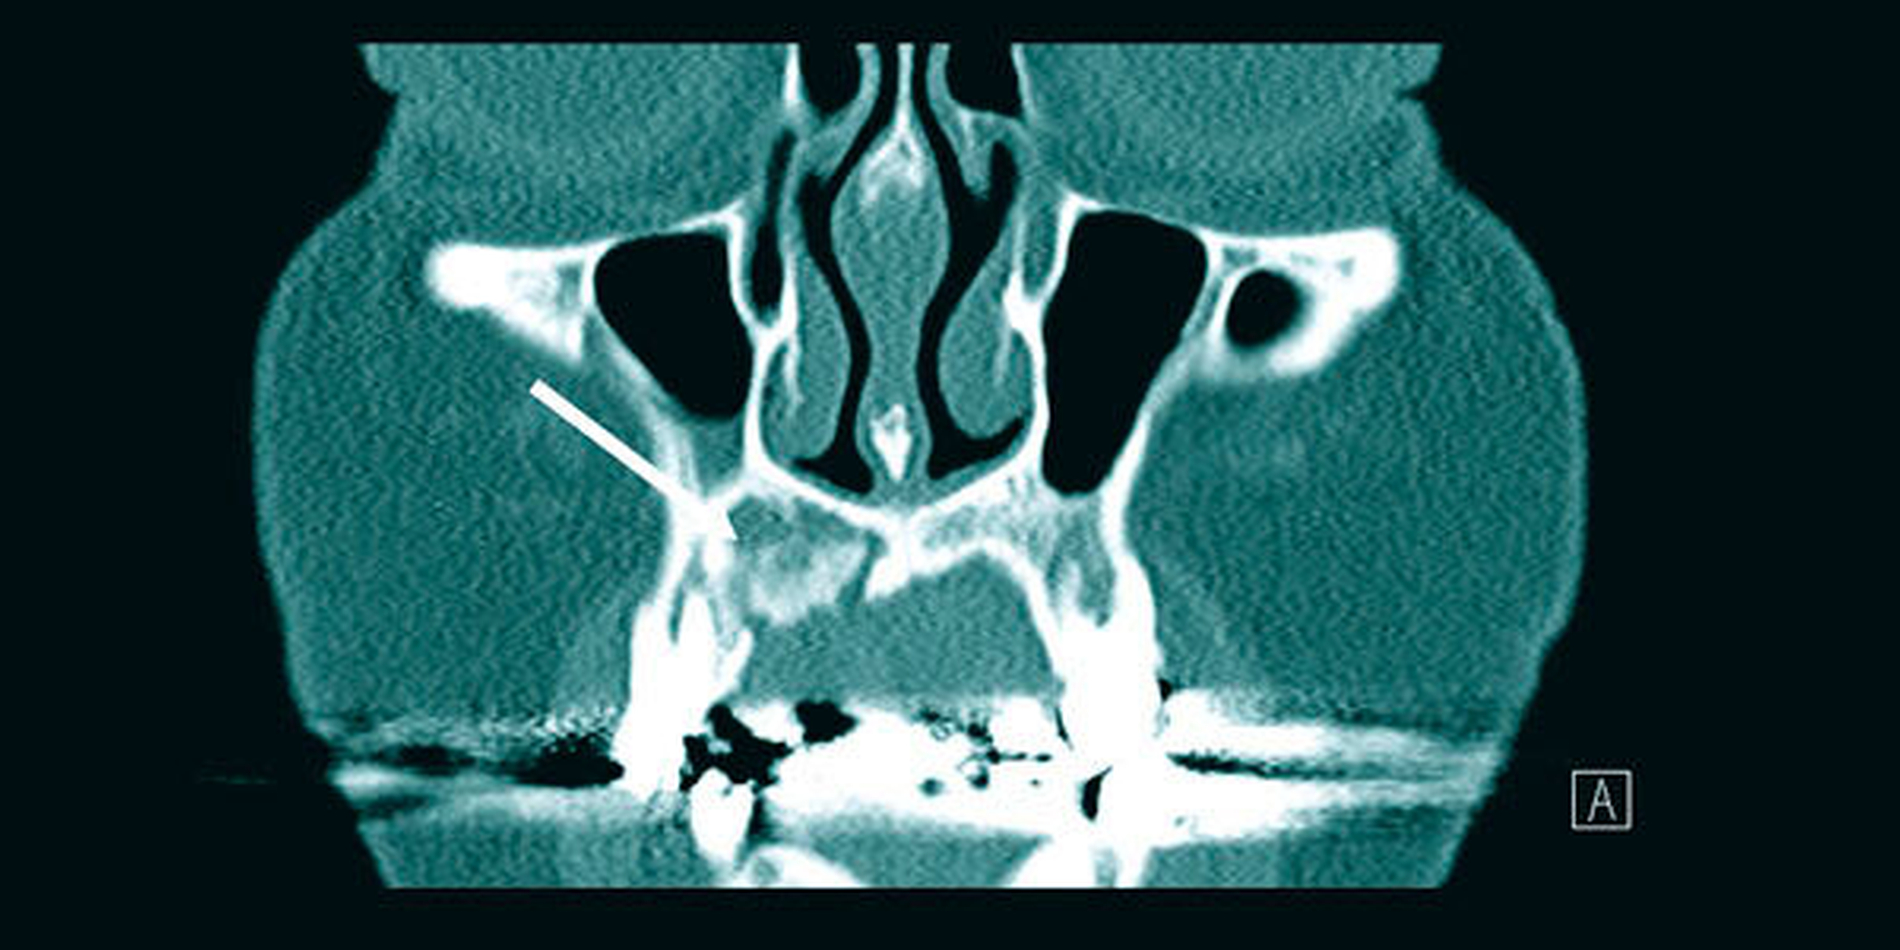

In der Diagnostik kommt demnach neben der eingehenden oralen Inspektion der bildgebenden Untersuchung eine zentrale Bedeutung zu. Hierbei ist zu beachten, dass eine klassische konventionelle Panoramaschichtaufnahme als unzureichend gilt und – gerade auch im Sinne einer präoperativen Diagnostik – durch geeignete 3-D-Verfahren zu komplettieren ist. Außerdem wird empfohlen, eine histopathologische Aufarbeitung des Gewebes durchführen zu lassen, um zum einen maligne Prozesse ausschließen zu können und zum anderen die Diagnose zu sichern.